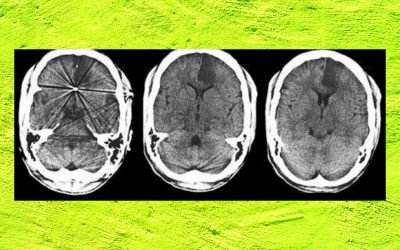

Young Doctor with Recurrent Stroke: A Diagnostic and Therapeutic Dilemma.

CME INDIA Case Presentation Dr Deepak Gupta, DM, FESC, FSCAI, FACC, Director Cardiac Sciences Pulse Superspeciality Hospital, Ranchi. CME INDIA Case Study: 50yr old male develops CVA while swimming in club at Varanasi, strong family history of stroke in young. He is...